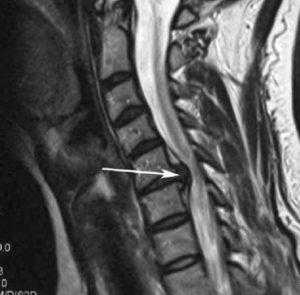

Компрессионно-вертебральный синдром включает в себя серьезные неврологические расстройства. Они сопровождаются мучительными локальными и/или отраженными болями в спине и других участках тела, нарушениями чувствительных и опорно-двигательных функций конечностей, дисфункцией внутренних органов, в частности органов малого таза. Эти симптомы чаще вызывают дегенеративно-дистрофические заболевания (запущенный остеохондроз в 80%), посттравматические осложнения и опухоли, которые спровоцировали сужение полости спинномозгового канала. Как следствие, на нервные волокна и сосуды начинает воздействовать фактор патологического давления и тканевой травматизации, что выражается вышеперечисленными признаками.

Стеноз шейного отдела вследствие грыжевого выпячивания.

С лечением компрессии шейного отдела позвоночника, пояснично-крестцового или грудного, медлить нельзя! Долгое компрессионное воздействие может вызвать гибель жизненно важных структур, в итоге привести к параличу рук или ног, тяжелым необратимым мозговым нарушениям, критической несостоятельности мочеполовой системы, сердца, дыхательного центра. Профессионально оценить всю серьезность клинического случая, грамотно рекомендовать тот или иной вид терапии, может - невролог, нейрохирург, ортопед.

Вмешательство заключается в хирургическом устранении патологических дефектов, вызывающих перекрытие канала позвоночника, сдавливание нервных и сосудистых образований. Это могут быть межпозвонковые грыжи, краевые костные разрастания позвонков, гипертрофированные связки, доброкачественные или злокачественные новообразования, гематомы, спайки.